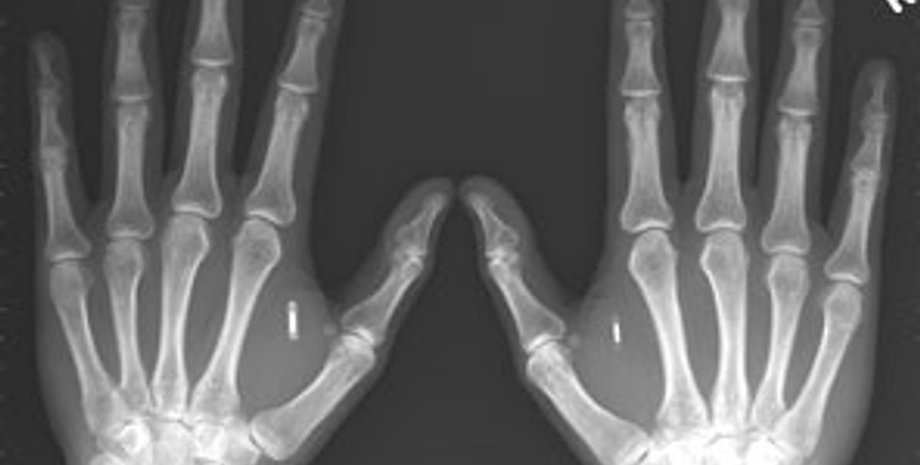

Исследователи рассчитывают, что этот клей произведет небольшую революцию в травматологии. Дело в том, что сломанную кость крайне трудно срастить - многие мелкие осколки не возвращаются на старое место. Это приводит ко многим проблемам. С помощью нетоксичного клея, способного действовать в агрессивной среде, эти осколки можно использовать и надежно закрепить. Кроме того, предполагается, что мощь клея будет столь значительна, что сломанная кость де-факто будет крепче целой. Клей также можно использовать для того, чтобы адресно доставить в место перелома необходимые медикаменты, например, антибиотики, обезболивающие препараты, гормоны и пр.